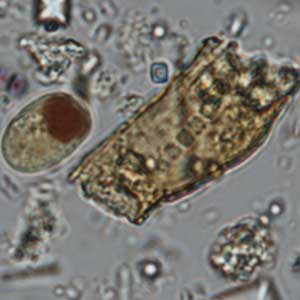

Les kystes de Iodamoeba butschlii sont ovalaires, à noyau rond, de diamètre moyen à grand, avec un nucléole large central à périphérique ; ce dernier n’est cependant pas toujours visible. Ils sont caractérisés par une vacuole iodophile volumineuse, excentrée, qui se colore franchement au Lugol, apparaissant brun-acajou. Ils mesurent 5 à 20 μm de longueur (Euzéby, 2008).

Les kystes de Iodamoeba butschlii sont en général facile à mettre en évidence par coloration de la vacuole iodophile au Lugol. Le diagnostic différentiel comprend les amibes de taille petite à moyenne dont les formes immatures d’Entamoeba histolytica qui peuvent aussi présenter une vacuole iodophile (Euzéby, 2008). Néanmoins, ces kystes immatures sont arrondis, ils présentent un à quatre noyaux de type Entamoeba, la vacuole iodophile, si elle existe, est moins colorée au Lugol, et ils possèdent des cristalloïdes que n’ont pas les kystes de Iodamoeba butschlii (Euzéby, 2008). Ces détails sont davantage visibles par coloration au trichrome ou à l’hématoxyline ferrique.